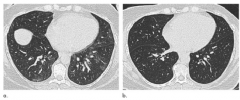

肥胖与肺功能之间的关系

近日,发表在Radiology杂志的一项研究评估了减肥手术前和术后6个月肺实质和气管的CT形态,并探讨了其与肺功能和临床症状之间的关系,为临床进一步阐明肥胖与肺功能之间的关系提供了有价值的参考依据…2021-05-11 08:35:45